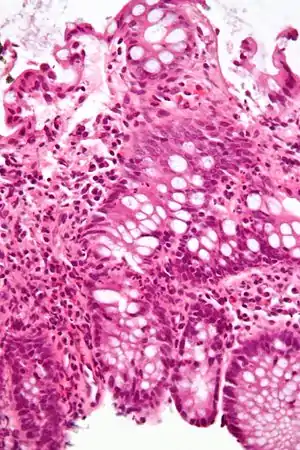

![]() Мікрофотознімок запалення товстої кишки. Фарбування гематоксиліном-еозином Мікрофотознімок запалення товстої кишки. Фарбування гематоксиліном-еозином | |